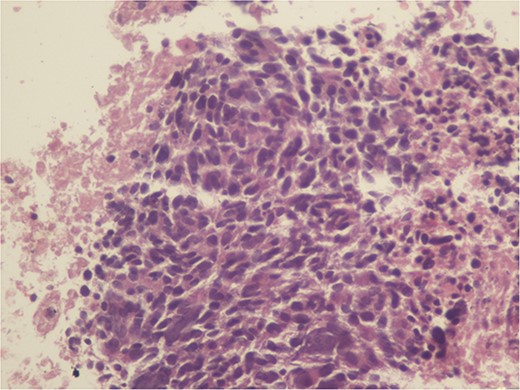

A 59-year-old woman presented with complaints of abdominal pain and abdominal distension for about a month. There was no known systemic disease and no history of previous abdominal surgery. It was learned that the patient had been admitted to the emergency department in another center one month ago with the current complaints and was discharged after medical treatment. Physical examination at the time of admission revealed abdominal distension and diffuse minimal tenderness with no signs of peritoneal irritation. Laboratory tests revealed that hemogram and biochemical parameters were within normal limits, but one of the tumor markers, the patient’s CA 19-9 level was significantly elevated at 855 U/ml (normal range: 0–37 U/ml). Contrast-enhanced CT scan showed a 10×10 cm heterogeneous mass in liver segments 4B-5, extending to segment 6, and free fluid adjacent to the liver and irregular liver contours. Borders of the gallbladder could not be seen. Soft tissues forming nodular mass formation were detected on the omental surfaces (Fig. 1). Computed tomography examination performed at the center where the patient was admitted as an emergency one month ago revealed hypodense lesions measuring 10×8 cm in size in the left lobe of the liver, protruding into the inferior perihepatic area, and 3.5 cm in diameter in segment 5 of the right lobe with no significant contrast enhancement after intravenous injection of contrast material. Perihepatic ascites was not detected and gallbladder size, wall thickness and lumen were normal (Fig. 2). In the light of the radiologic findings, a pre-diagnosis of progressive gallbladder malignancy was considered. The patient was hospitalized in the General Surgery ward for further investigation and treatment. Because of the presence of ascites causing abdominal distension, a percutaneous ascites drainage catheter was placed and 5000 cc ascites drainage was performed. Cytologic examination of the ascitic fluid revealed cell groups with unclear three-dimensional cytonuclear detail among lymphocytes and mesothelial cells with reactive atypia and malignancy was considered suspicious. With the current radiologic and cytologic findings, inoperable metastatic gallbladder carcinoma was considered. Medical treatment was decided by the multidisciplinary oncology council and 18G needle tru-cut biopsy was performed from the 10×10 cm mass adjacent to the gallbladder for definitive tissue diagnosis and adjuvant treatment planning. Histopathologic examination revealed a diagnosis of neuroendocrine carcinoma (NEC) (Fig. 3). Immunohistochemical examination revealed strong staining of tumor cells with CD56 (Fig. 4), synaptophysin (Fig. 5), chromogranin A (Fig. 6), and Ki67 index was >90% (Fig. 7). Weak staining was observed with CK19, CK7, and CDx2, but no staining was observed with CEA and CK20. Morphologic findings were compatible with small cell type. Etoposide and cisplatin chemotherapy was planned but the patient’s general condition deteriorated progressively. The patient couldn’t start chemotherapy and unfortunately resulted in mortality on the 20th day of hospitalization.